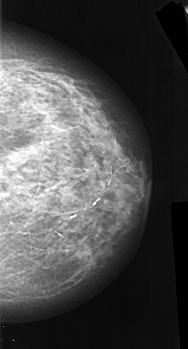

A_1019_1.LEFT_MLO

LEFT_MLO LINES 5776 PIXELS_PER_LINE 3211 BITS_PER_PIXEL 16 RESOLUTION 42 OVERLAY